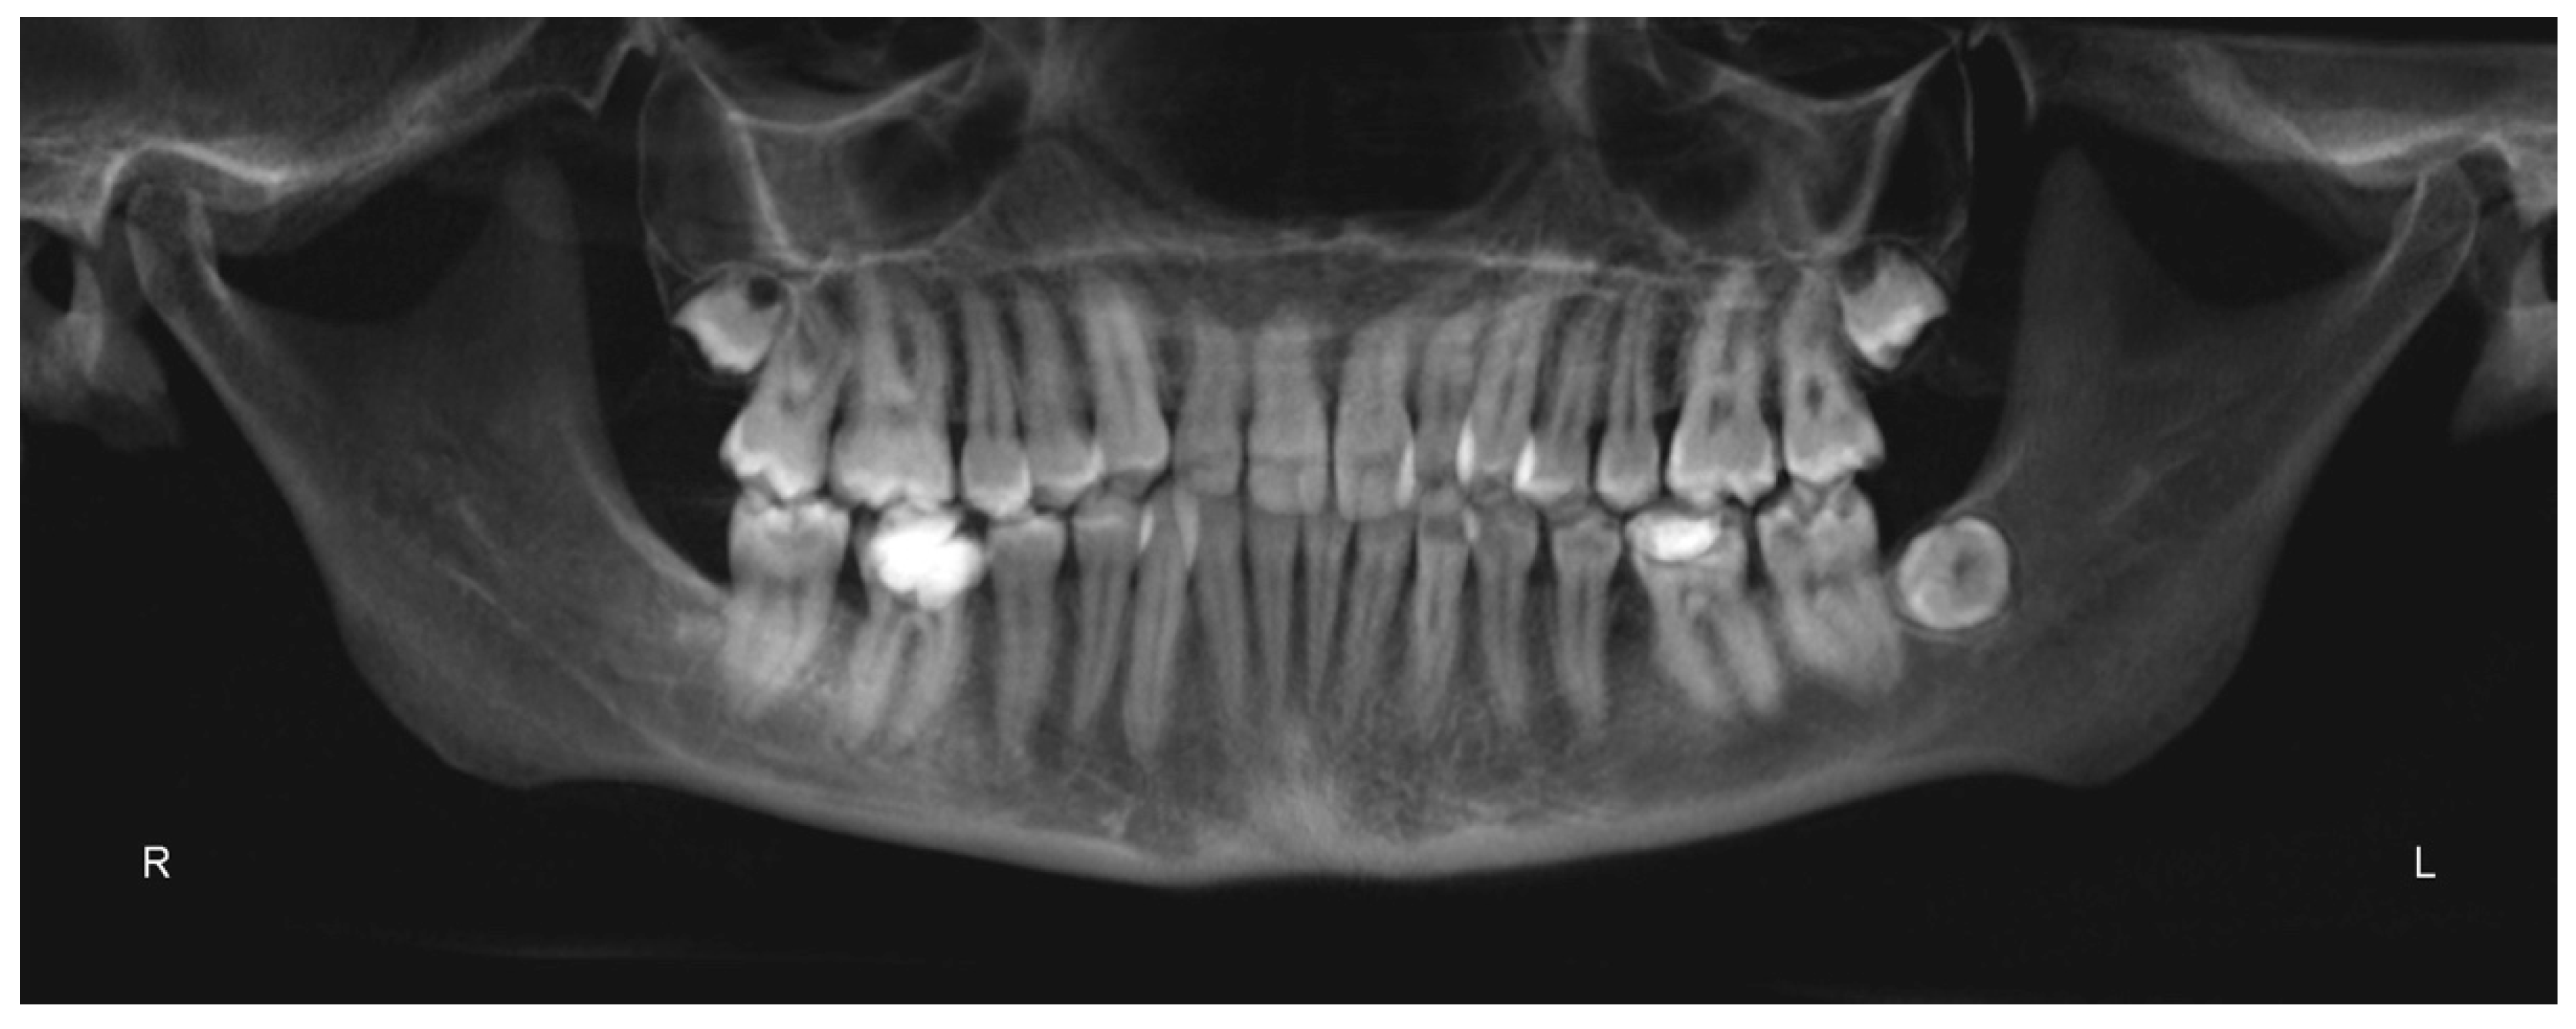

3.1. Diagnosis and Treatment Plan

3.2. Digital Workflow for Planning MSE Device